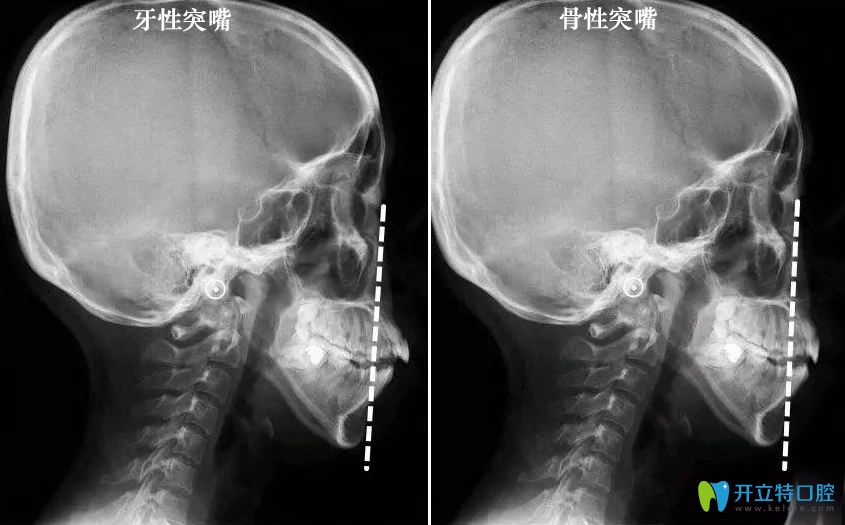

那么,怎么樣判斷嘴凸是骨性還是牙性?一眼讓你看明白!

【骨性突嘴和牙性凸嘴判斷對(duì)比圖】:↓↓

骨性突嘴和牙性凸嘴判斷對(duì)比圖

郭醫(yī)生表示,嘴凸牙性和骨性的區(qū)別在于,

單純的牙性突嘴,僅有牙齒向前突,?

牙齒長(zhǎng)軸角度傾斜過(guò)大,上唇和鼻子周圍是不鼓的。

而骨性突嘴,牙齒的上頜骨,還有鼻子周圍都是向前鼓的,

并且露出的牙齒比較多,從面相上來(lái)看,嘴唇是包不住牙齒,

骨性齙牙在笑的時(shí)候很明顯,有些整顆牙齒和牙齦會(huì)露出來(lái)。